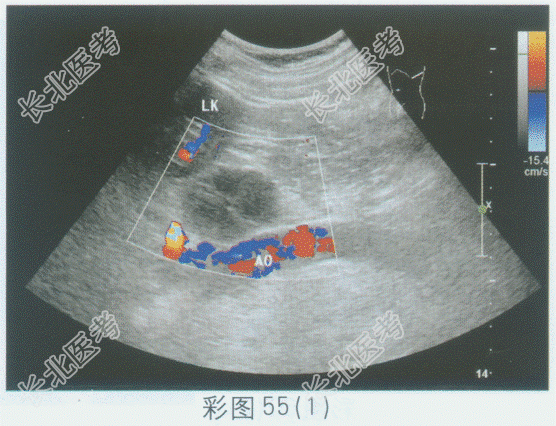

超声综合描述: 左肾下极与腹主动脉之间可见不均质低回声,与腹主动脉关系密切, 边界清晰,形态规则, 内可见形态不规则无回声,CDFI: 其内及周边均未见动静脉血流信号。见下图及彩图55。

超声提示: A、腹膜后囊实性占位(神经鞘瘤)